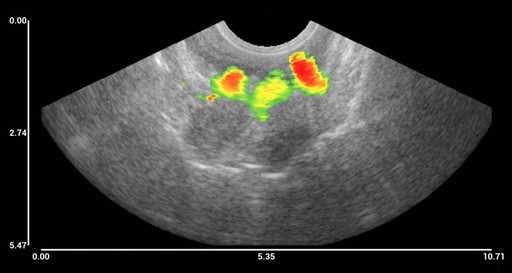

Bild 1 (se bifogad bild) Magnetomotorisk ultraljudsbild av järnoxidbaserade nanopartiklar i mänsklig vävnad. Före operationen injicerades patienten med nanopartiklar och det utopererade vävnadsprovet avbildades. De tre färgade områdena motsvarar de tre injektionsställena (1).

Den vetenskapliga publikationen är baserad på omfattande mätningar i laboratoriemiljö, samt en undersökning av en patient med rektalcancer som genomgår en rektalcanceroperation. Innan operationen fick patienten järnoxidbaserade nanopartiklar injicerade på tre ställen nära tumören. Patienten genomgick därefter den planerade operationen och den del av ändtarmen där cancertumören fanns avlägsnades tillsammans med närliggande lymfkörtlar, enligt sedvanlig klinisk praxis. Efter ingreppet undersöktes den utopererade vävnaden med NanoEchos prototypsystem och på ultraljudsbilden syntes nanopartiklarna tydligt vid samtliga tre injektionsställen.